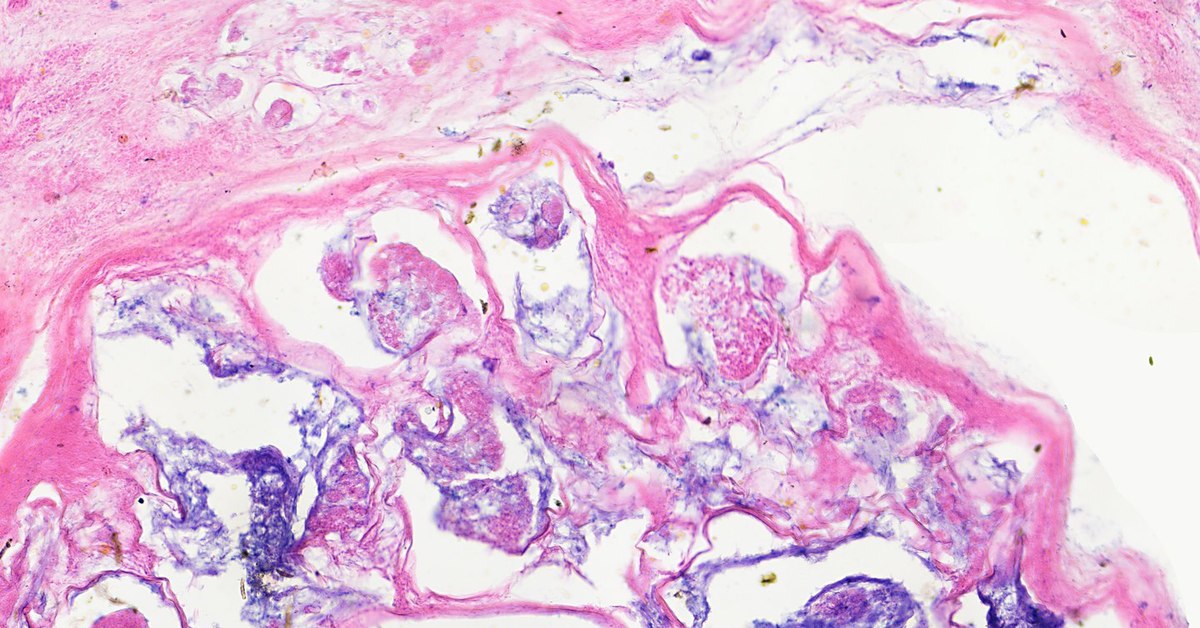

Фотографии опухоли медуллярной аденокарциномы

Раздел: Снимки-откровения